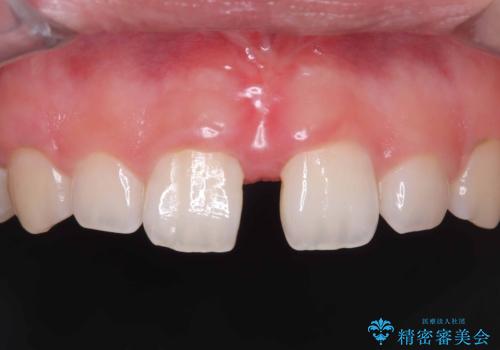

- 「舌が短くて滑舌が悪いので舌小帯を切って欲しい」を主訴に来院された患者様です。

舌小帯切除術を行い舌の可動域を広げ、滑舌の向上を目指しました。

短い舌小帯に舌が引っ張られて舌がハート型になっています。